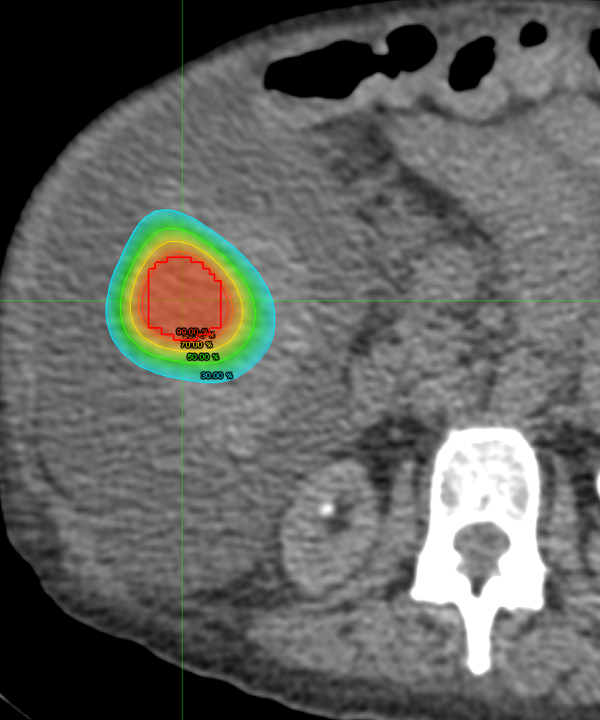

Renal upper pole lesion ablations

Renal upper pole lesions are theorized to be more difficult to ablate and potentially with lower rates of disease control and higher risks of complications. We are doing a retrospective chart review project to demonstrate that ablations of renal upper pole lesions are just as safe and effective.